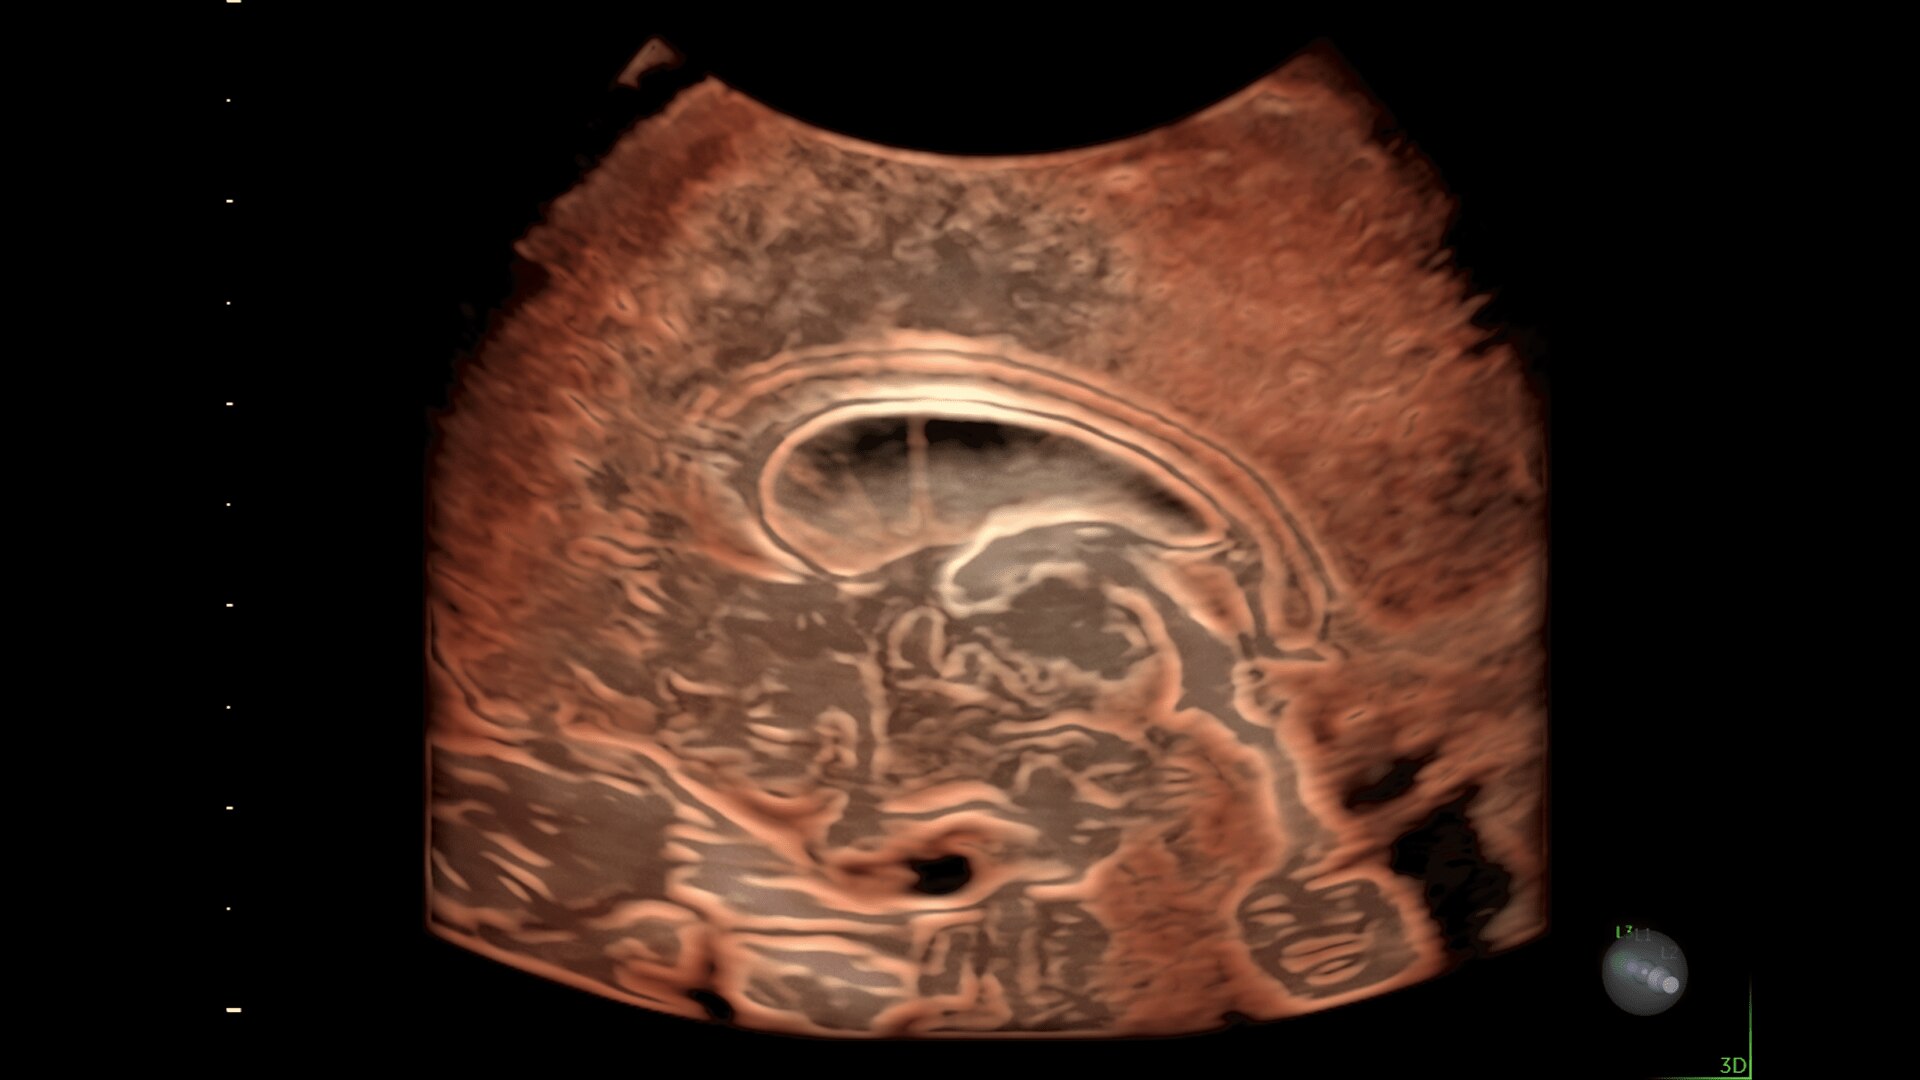

Eccezionale qualità immagine con esami a misura di paziente

PRESTAZIONI IQ OTTIMIZZATE